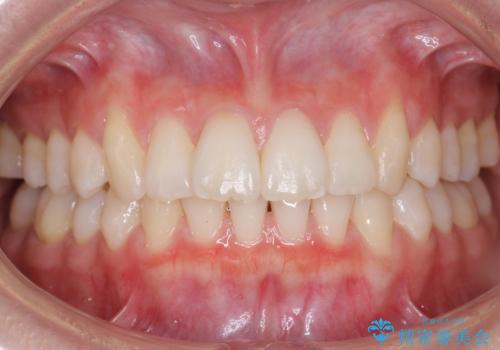

[ インビザライン ] 目立たないマウスピース矯正で、前歯のがたつきをきれいにしたい

担当医 大元洋佑

![[ インビザライン ] 目立たないマウスピース矯正で、前歯のがたつきをきれいにしたいの症例 治療前](https://seimitsushinbi.jp/wp/wp-content/uploads/2024/04/IMG_3912-500x350.jpg?v=1711960039)

![[ インビザライン ] 目立たないマウスピース矯正で、前歯のがたつきをきれいにしたいの症例 治療後](https://seimitsushinbi.jp/wp/wp-content/uploads/2024/04/cd64e6566cc0683feee2abf20f8241f9-500x350.jpg?v=1711960118)